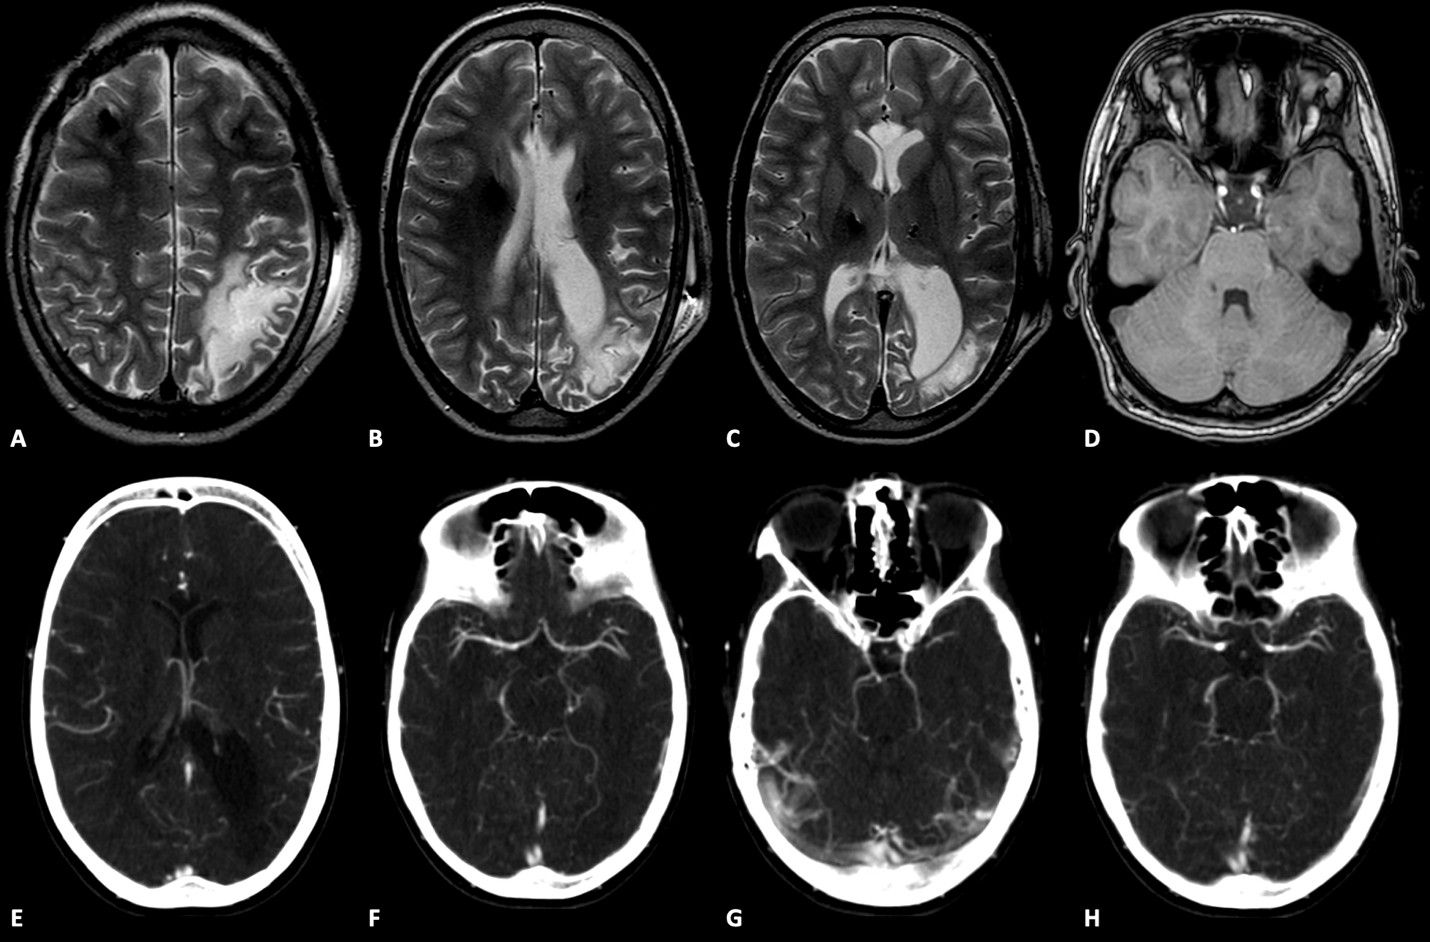

Results: A previously healthy 3-year-old girl developed status epilepticus after a febrile illness in the context of a left MCA and PCA AIS, leading to permanent visual deficits and refractory epilepsy. Despite multiple treatments seizures persisted. At age 6, whole exome sequencing identified a pathogenic CACNA1A variant. She exhibited right-sided hemiparesis, non-progressive ataxia, nystagmus, cognitive impairment, autistic traits, and behavioral disturbances. Acetazolamide improved her ataxia enabling ambulation.

Figure 2. MRI encephalomalacia right MCA-PCA.